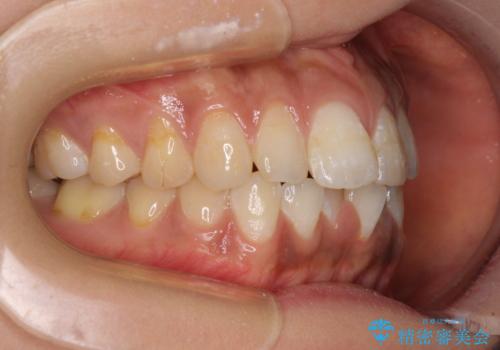

- 前歯のデコボコと上下前歯の隙間を気にして来院された患者様です。

下顎前歯はデコボコのため、歯肉が腫れやすくなっていました。

また、舌突出癖のため、上下前歯の間に隙間ができてしまい、上顎前歯が前方に傾斜している状態でした。